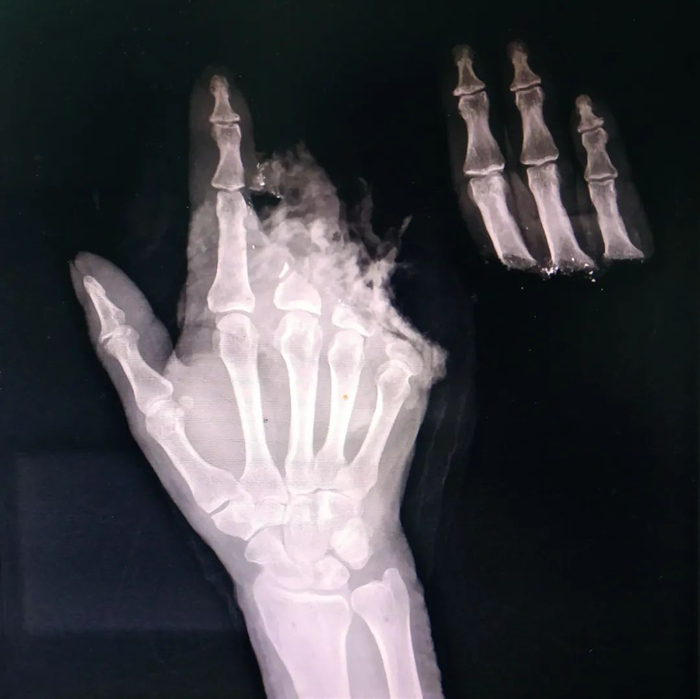

李芸右手断指再植入后图像。供图/无锡市第九人民医院

62岁的李芸右手三指截断,手术前影像(手背朝上)。供图/无锡市第九人民医院

在给李芸做的手术中,钱俊先要给其清创,将铁屑等创面上的异物去除,避免造成感染,然后用克氏针(一种钢针)将李芸截断的骨骼和断指处还保有的骨骼串起来,固定回原位,这好比房子重建时要用钢筋先搭起框架。

在骨骼固定后,他将李芸被利器斩断缩回手掌的肌腱找出,再需缝合每根断指承担手指伸屈功能的两根肌腱、两根动脉、两根静脉及两根神经。血管吻合是关键。手指血管形态宛如树木伸出枝桠,指根部血管较粗,直径为1毫米,指尖部位只有0.3毫米左右。缝血管的线至少在微米级别,比头发丝还细,放在桌上根本难以看出。缝合好后,一般要观察7-10天,保证血运通畅,避免血管痉挛或者血管里形成血栓。